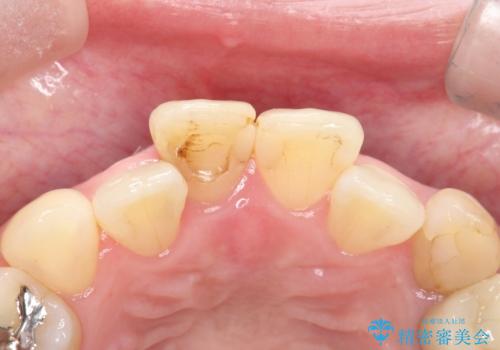

【オールセラミック】前歯の色を変えたい。

- 前歯の色が変色してきたことを主訴に来院されました。

根管治療から被せものまで治療を行いました。